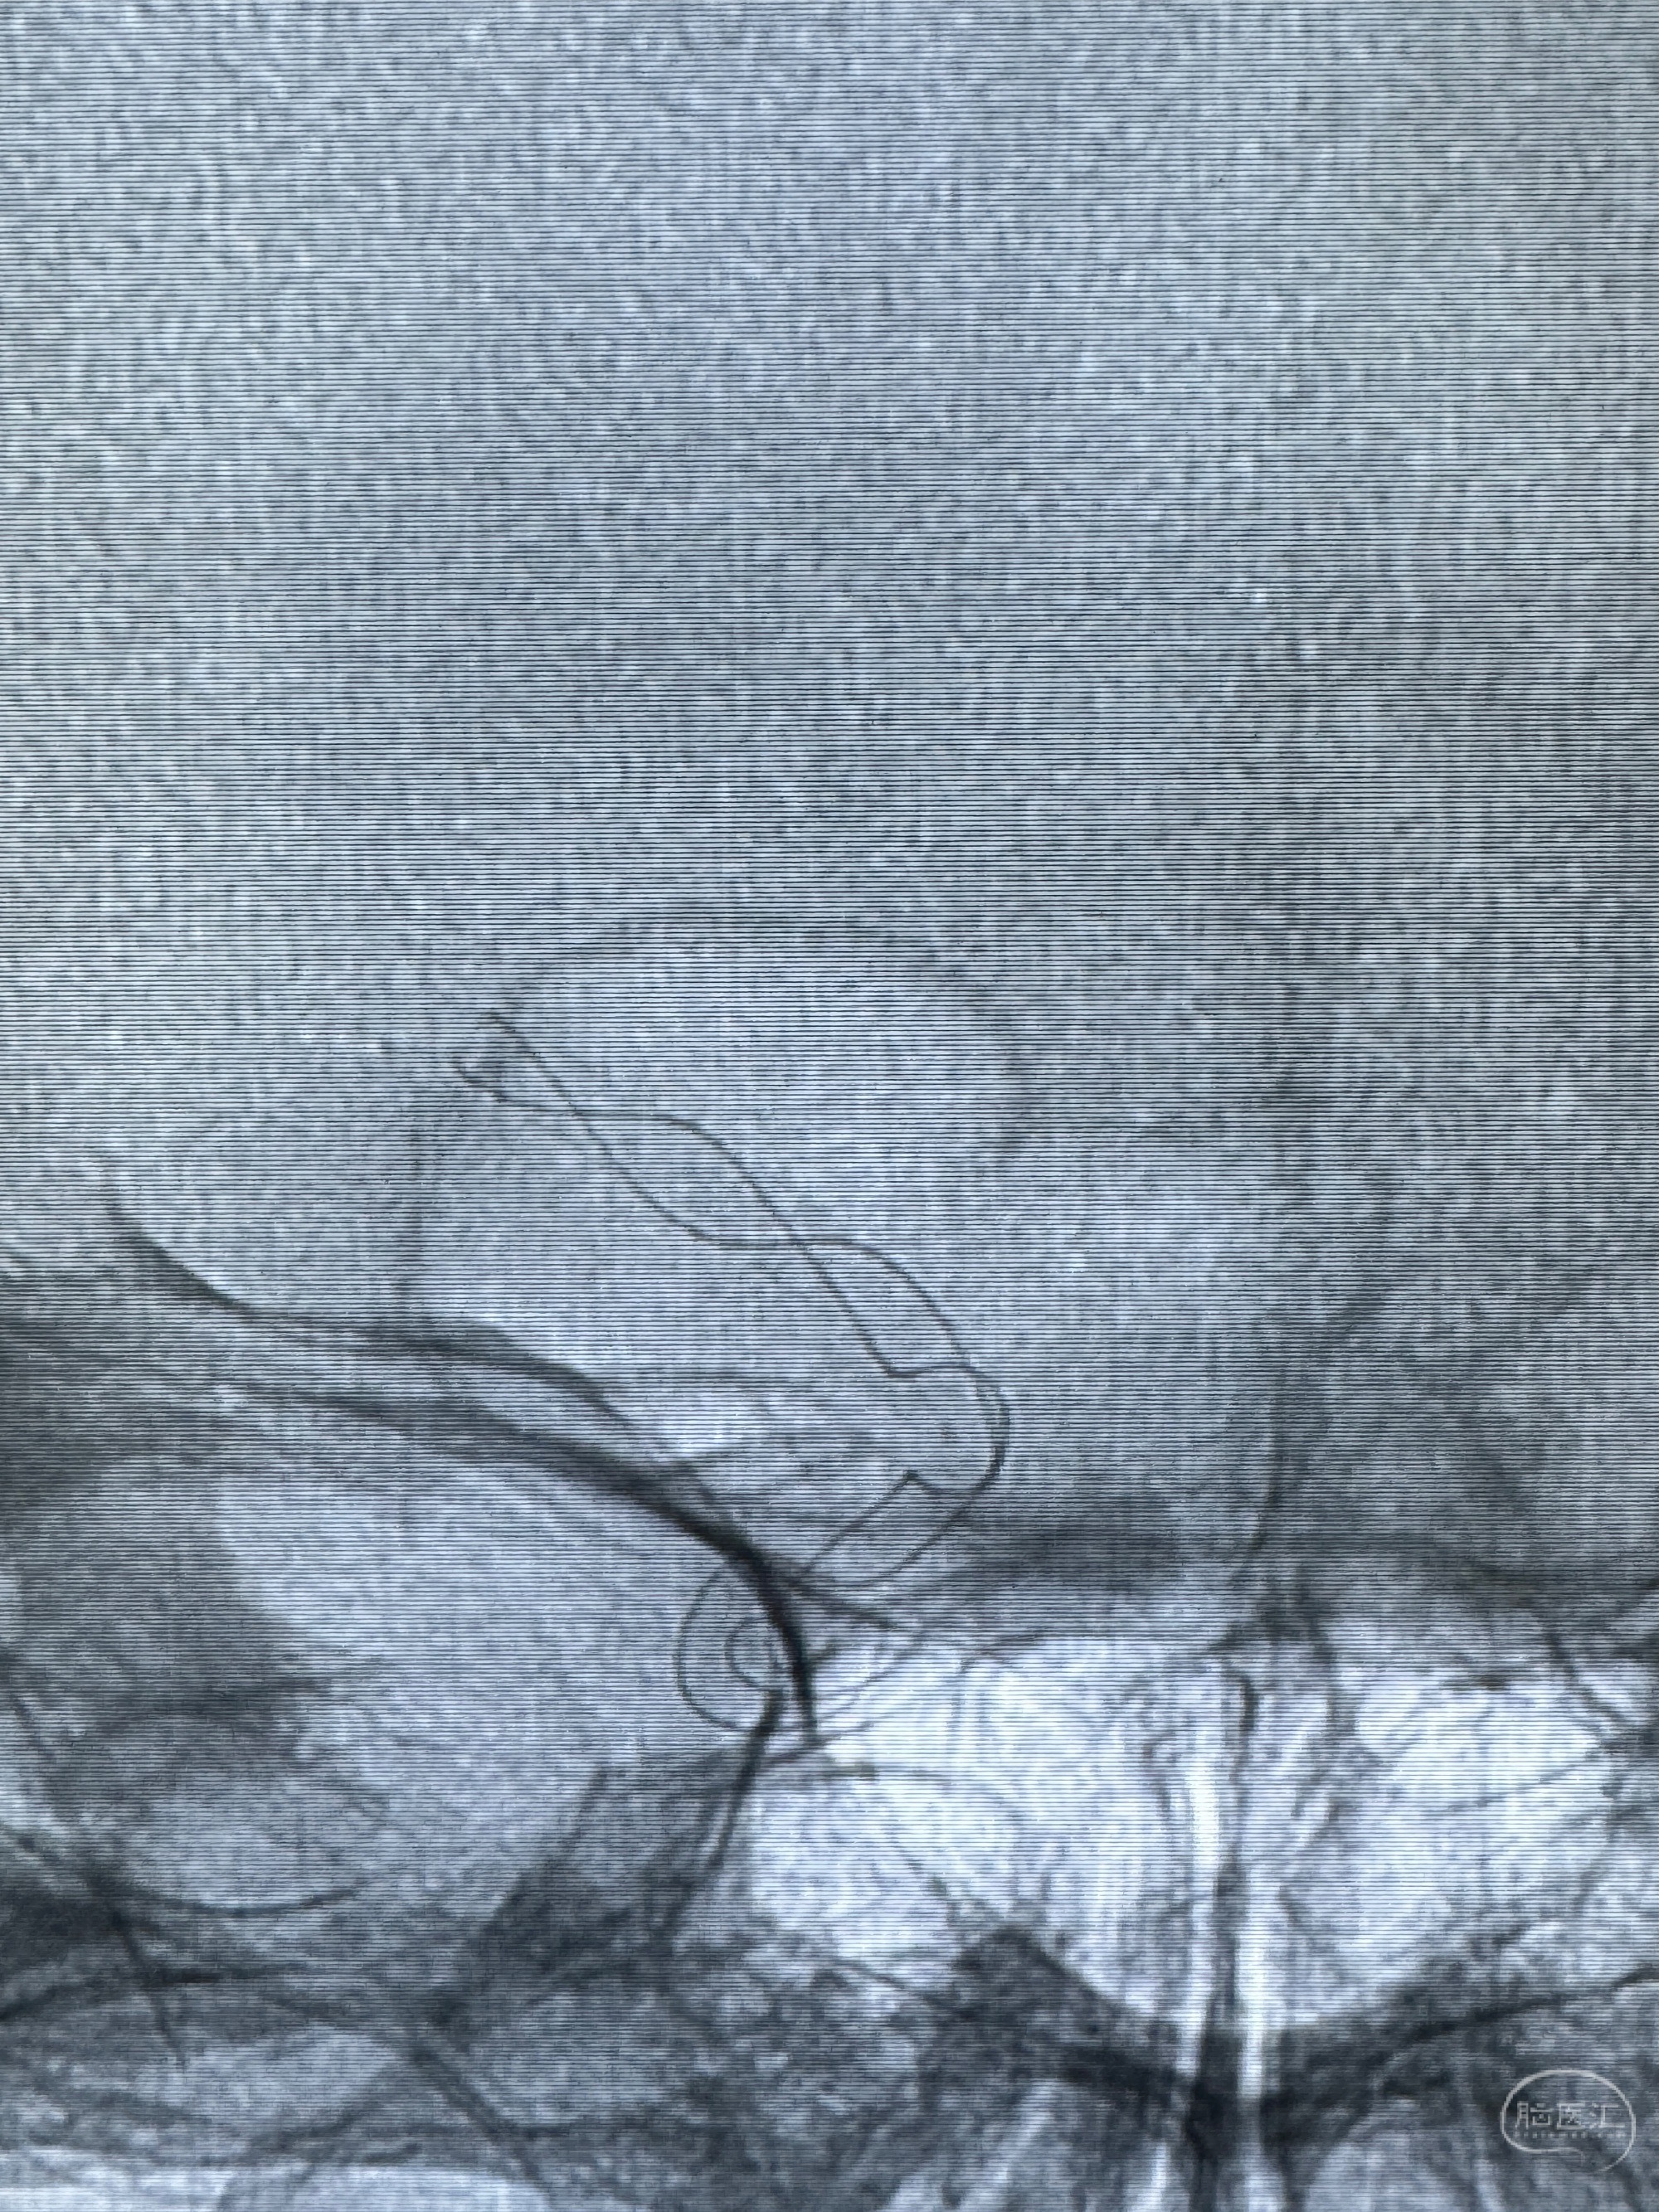

透视可见红圈部分为支架导管的头端

手推冒烟显示支架位置及展开情况,箭头为支架导管的位置

逐帧图像展示歪着脖子释放支架,旁边吩咐助手手机摄影、拍照留像(透视机不能留影像)

接下的视频为释放支架的过程及试图确认支架与血管的关系

好事者拍摄的术中使用小C臂处理危情的时刻